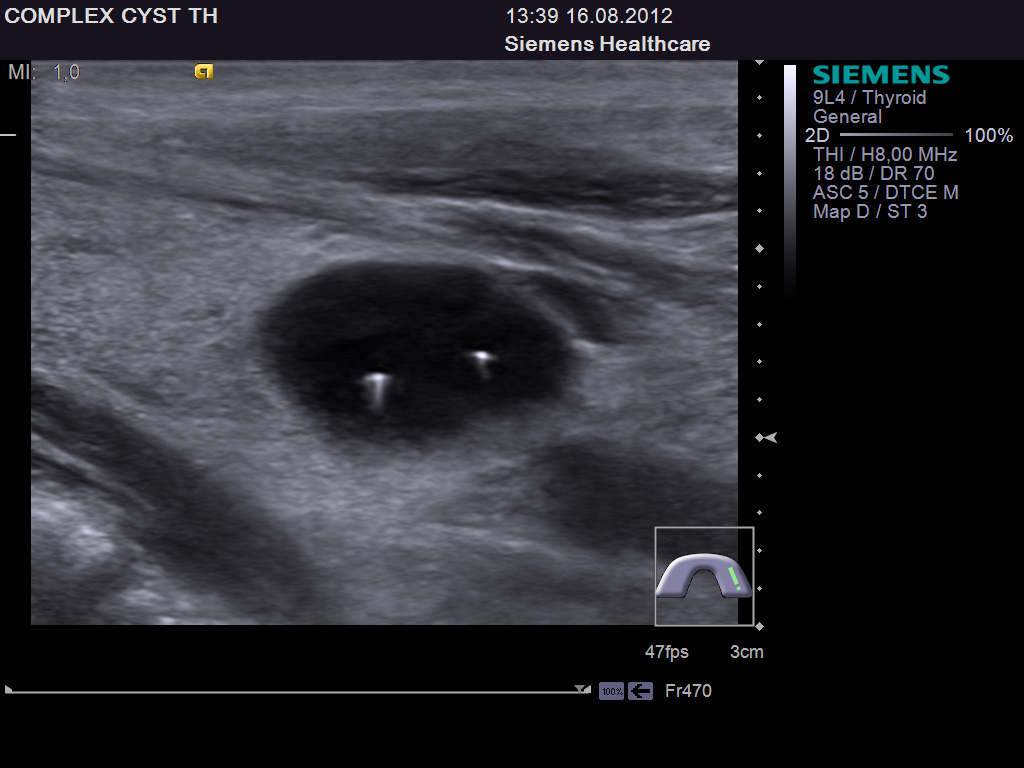

TI-RADS 4. Узлы более 1,0 см в диаметре с “малыми” признаками злокачественности для выполнения ПУНКЦИИ (рис. 3):

Рис. 3. TI-RADS 4: а – узел шаровидной формы, с ровными и четкими контурами, умеренно пониженной эхогенности, с участками более низкого эхо, с макрокальцинатом. Узел окружен тонким хало (фолликулярная неоплазия); б, в, г (поперечное и продольное сканирование левой доли ЩЖ) – изоэхогенные узлы с гипоэхогенными включениями, с четкими контурами, с тонким хало (фолликулярная аденома); д – изоэхогенный узел с гипоэхогенными включениями, с неравномерно утолщенным хало (фолликулярный рак).